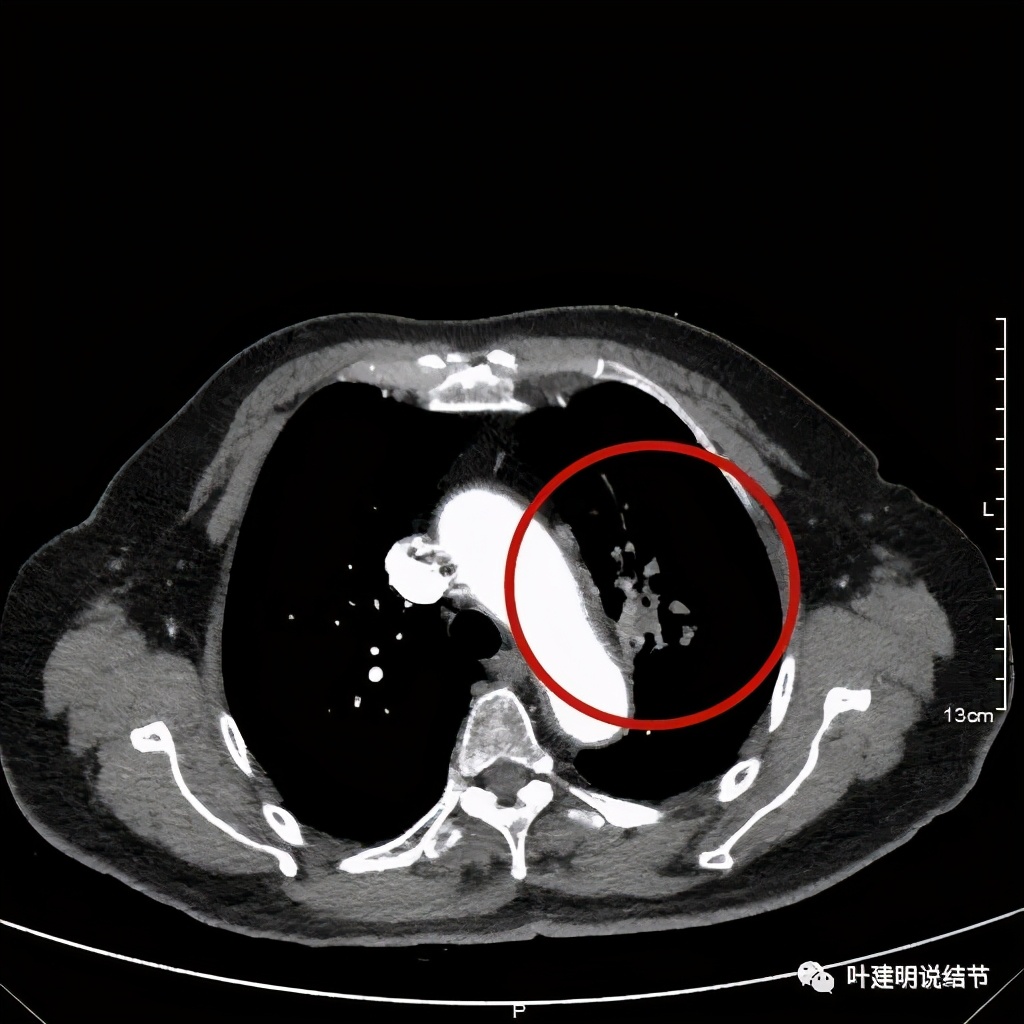

上图示主动脉弓水平仍见软组织影

上图桔色箭头示左肺动脉分支处仍被软组织(原肿瘤所在)包绕,粉色箭头示肺动脉仍与肿瘤处关系密切